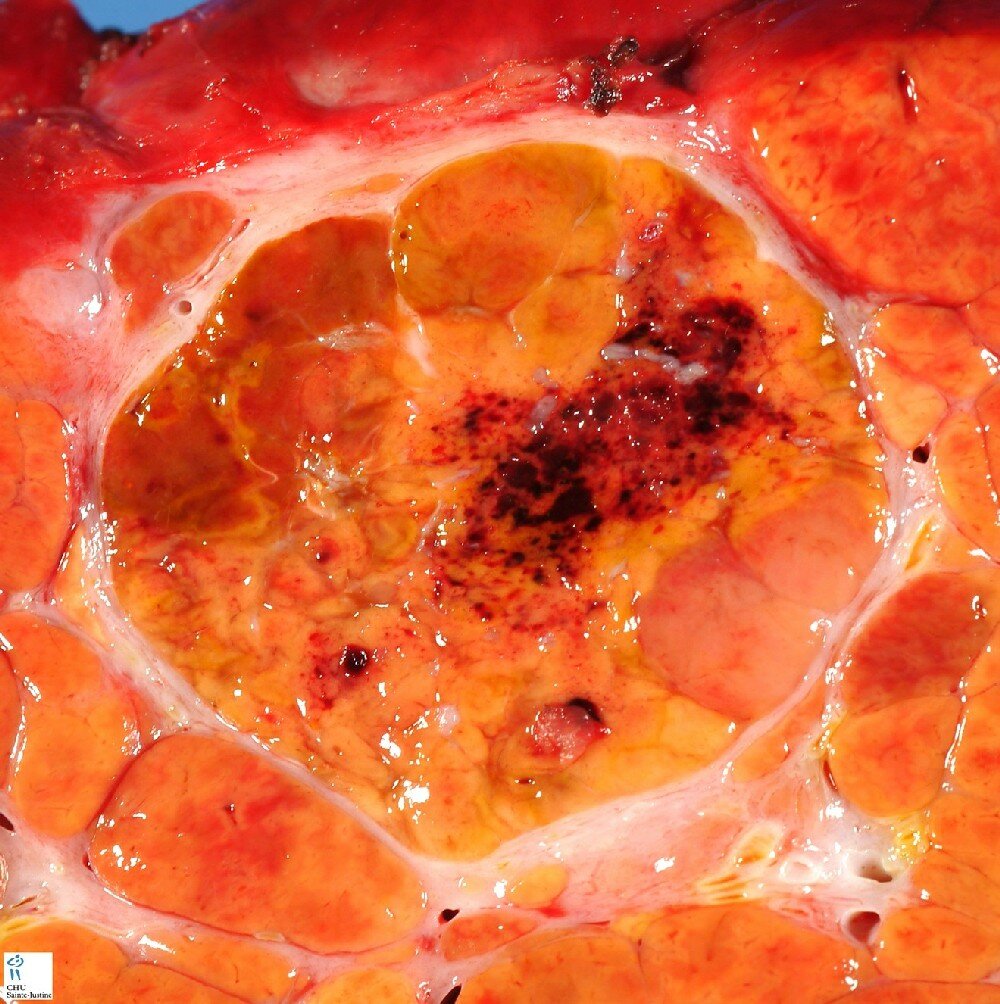

macronodular cirrhosis